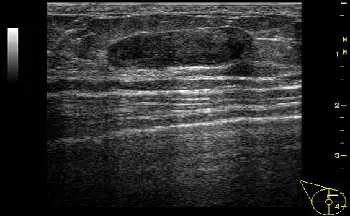

15 歲女孩乳房超音波檢查呈現病灶如附圖,最有可能的診斷為下列何者?

本題附圖為乳房 B-mode(灰階)超音波影像:

- 病灶形狀:橢圓形(oval),邊界清晰(well-circumscribed)

- 方向:平行於皮膚(parallel orientation),呈橫向排列

- 回音性:均勻低回音(uniformly hypoechoic)

- 邊緣:光滑、規則,無毛刺(smooth, regular margins without spiculation)

- 後方回音:無明顯增強或衰減(no significant posterior features)

- 周圍組織:無侵犯或破壞跡象

- 尺寸:中等大小(約 2–3 cm 估算)

影像判讀結論:橢圓形、界限清楚、均勻低回音、平行方向的實質腫塊,為良性纖維腺瘤的典型超音波表現(BI-RADS 3 類別)。

(A) 良性纖維腺瘤 ✅ 超音波表現:橢圓形、邊界清楚、均勻低回音、平行皮膚方向,完全符合纖維腺瘤的典型影像特徵。纖維腺瘤是 15